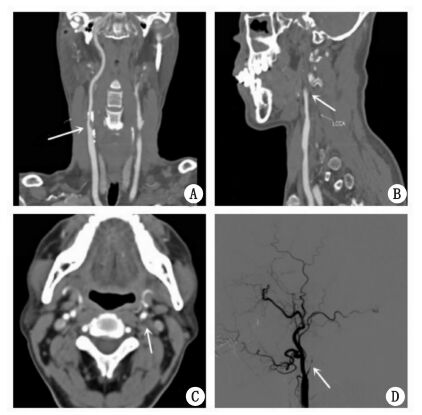

患者男,62岁,既往有高血压病及高脂血症病史,均未正规治疗。1个月前因突发左侧肢体无力就诊当地医院。入院后急性查头颅CT诊断右侧基底节区脑梗死,同时颈动脉彩色多普勒超声显示右侧颈内动脉起始部重度狭窄,左侧颈内动脉闭塞。住院期间每日予阿司匹林片100 mg抗血小板聚集治疗,阿托伐他汀片10 mg降血脂稳定斑块以及控制血压等对症治疗,15 d后患者病情稳定出院。本次患者为行右颈内动脉支架植入术(CAS)于2014年8月就诊本院。入院时患者除遗留左侧肢体肌力减退(上肢肌力Ⅲ级,下肢肌力Ⅳ级)外,无明显阳性局灶性神经症状及体征。本院颈动脉CT血管造影(CTA)进一步证实右侧颈内动脉起始部重度粥样硬化性狭窄,狭窄率约90%(图 1A),左侧颈内动脉起始部闭塞(图 1B1C)。头颅磁共振扫描显示右侧大脑基底节区新鲜脑梗死,左侧大脑半球实质未见缺血梗死灶。排除手术禁忌后,患者于入院第3天行经皮右侧颈内动脉支架植入术,术中DSA血管造影证实左侧颈内动脉完全闭塞(图 1D)。支架植入术过程顺利,术中共计使用普通肝素4 500 U。围手术期及术后患者均未出现手术相关并发症。术后3 d患者顺利出院。出院后患者每日口服阿司匹林片100 mg、氯吡格雷片75 mg抗血小板聚集治疗,阿托伐他汀片10 mg降血脂稳定斑块,同时给予口服降压药物降压治疗。

图 1 患者颈动脉支架植入术前颈动脉CTA(A、B、C)及术中左侧颈动脉DSA血管造影(D)